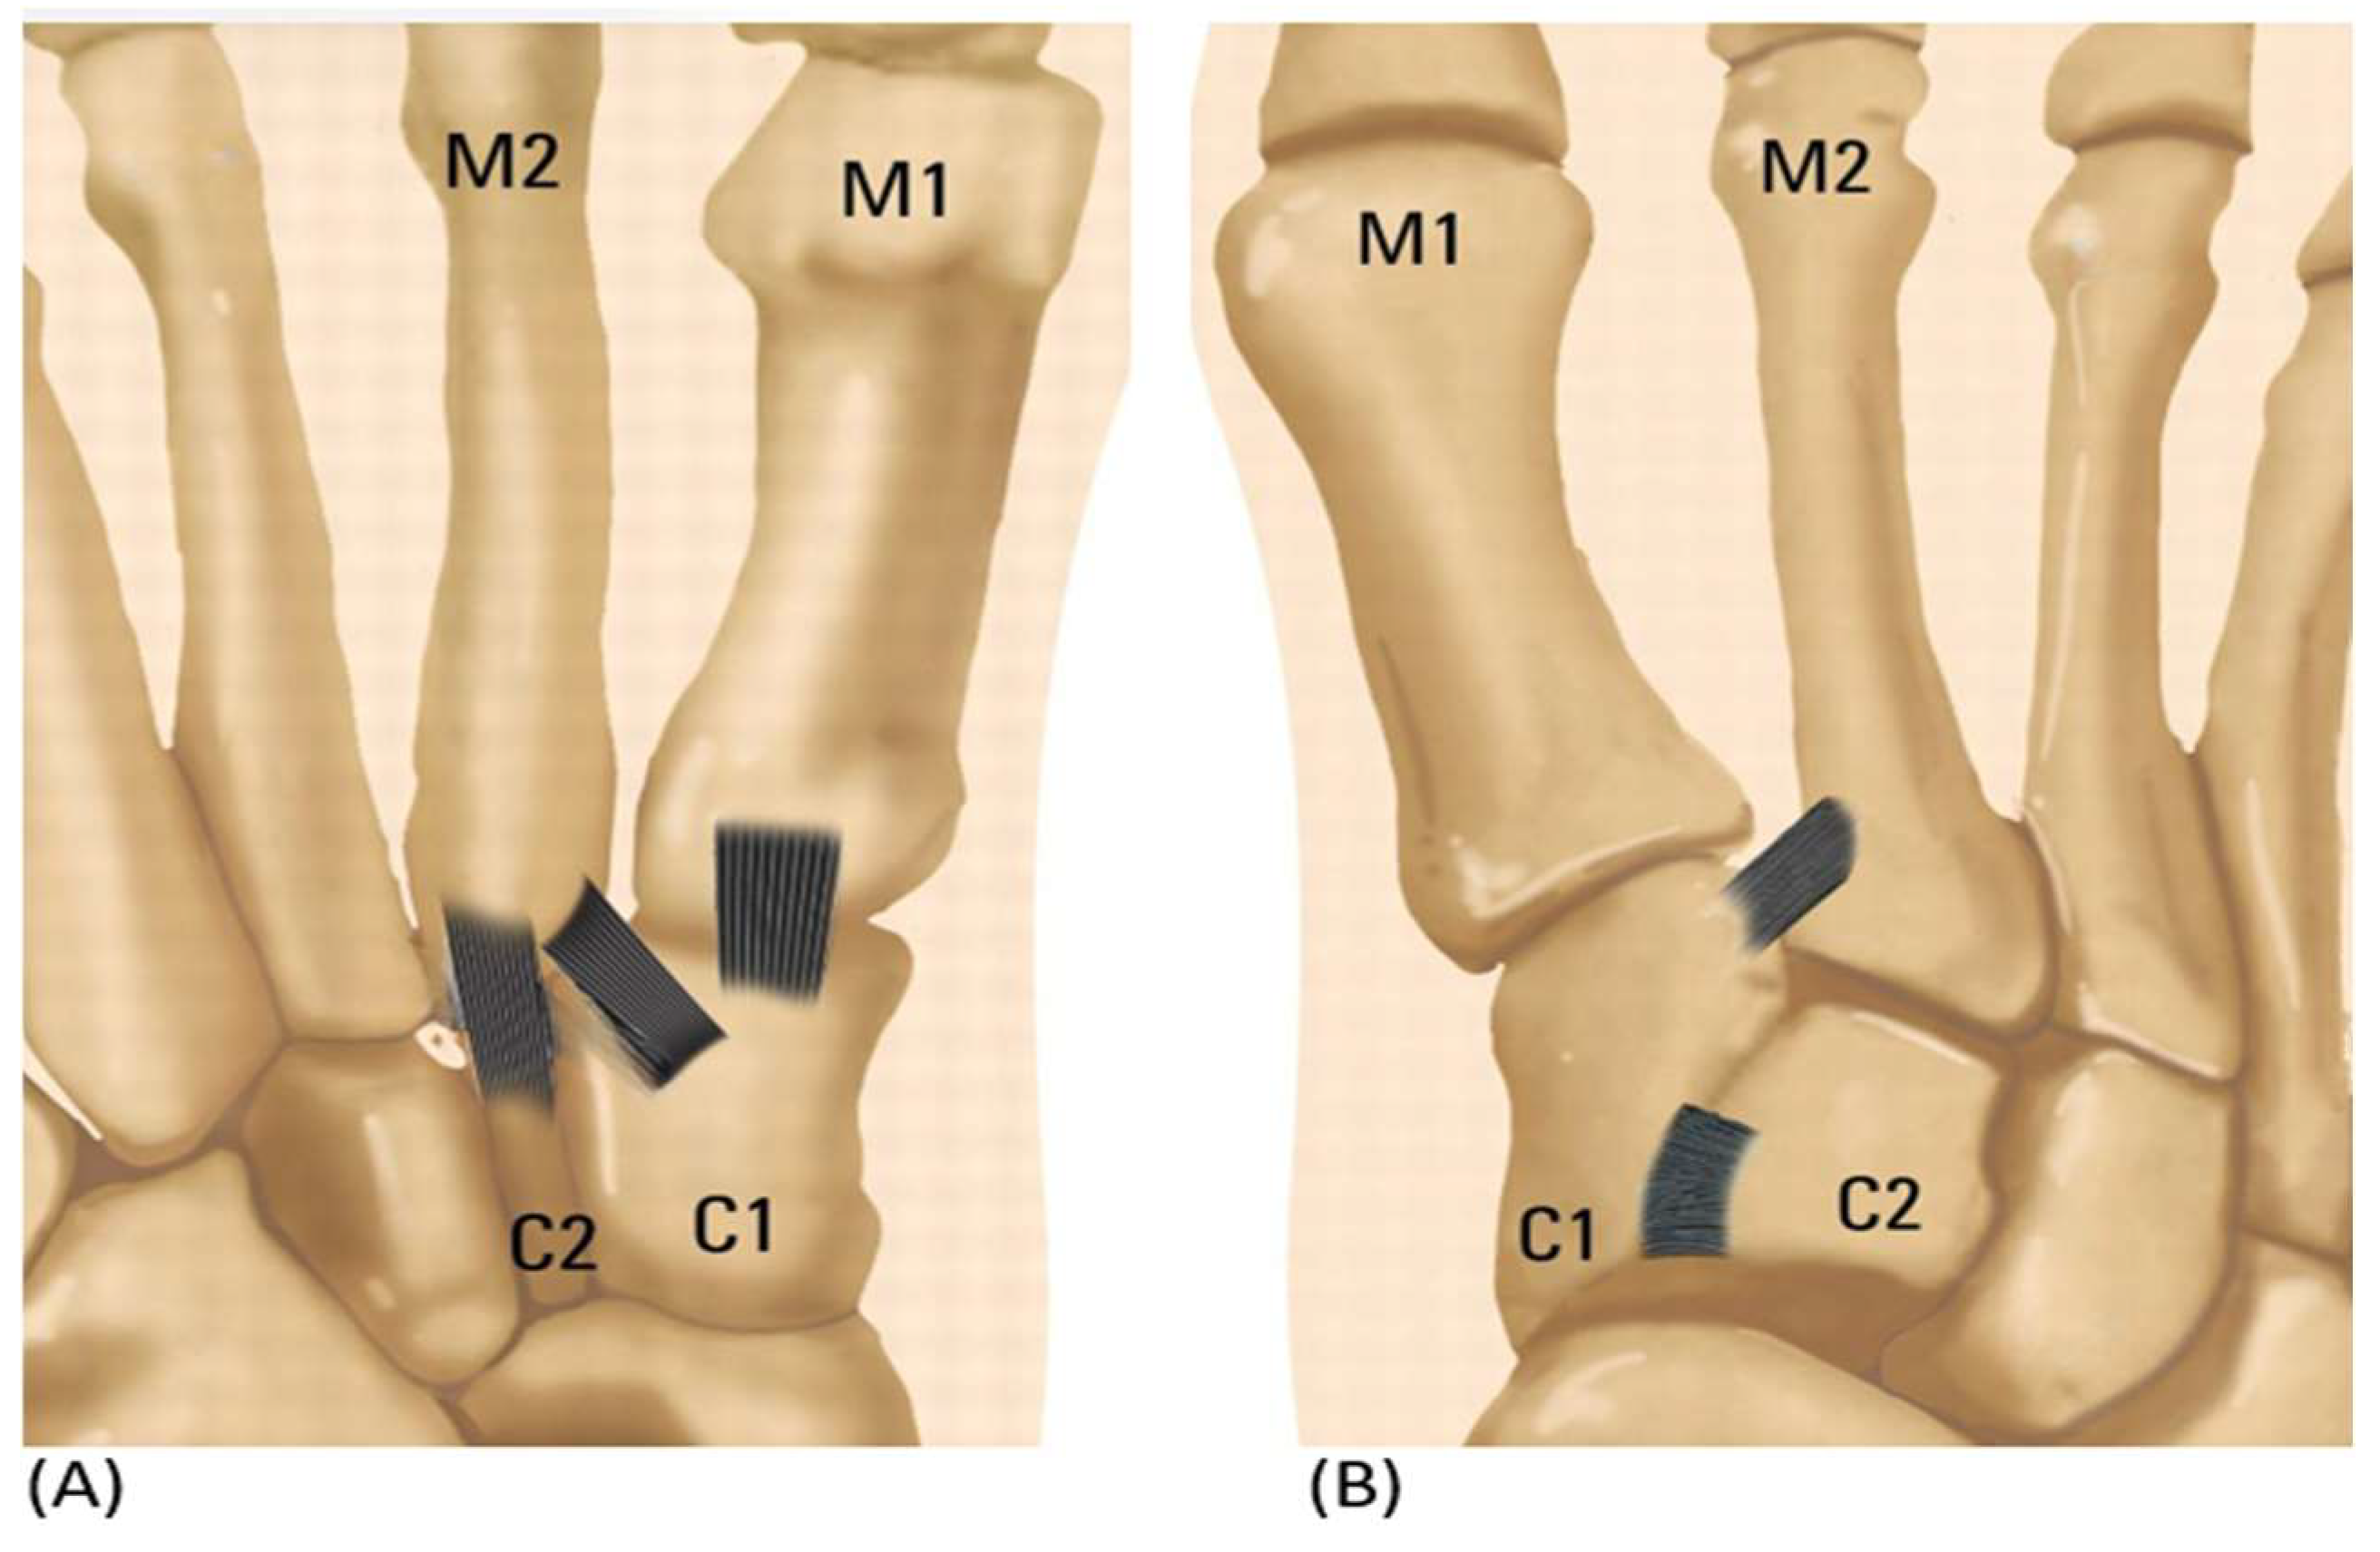

Prior categories, however, had certain drawbacks in that choosing a surgical technique was not made any easier. Therefore, a new categorization for modest Lisfranc injury based on anatomical configuration is required. Medial cuneiform (C1)—second metatarsal bone (M2) ligament damage with diastasis is one possible variation of isolated Lisfranc ligament damage. Other variations include medial cuneiform (C1)—intermediate cuneiform (C2) instability, medial cuneiform (C1)—first metatarsal bone (M1) instability, and intermediate cuneiform (C2)—second metatarsal bone (M2) (Table 2 and Figure 2) [16].

Figure 2. (A) A simplified illustration showing the anatomy of plantar sided ligamentous instability. (B) Isolated Ligamentous Lisfranc injuries reveal ligamentous instability in the dorsum.

According to the aforementioned types, a single tightrope may be preferred for C1-M2 injuries limited to diastasis [17], where damage with diastasis and the isolated Ligamentous Lisfranc injury are present. If C1–C2 instability is added [18] between medial cuneiform and intermediate cuneiform, a dual tightrope or internal brace may be preferred. Additionally, screw or plate fixation and reconstruction might be taken into consideration when there is joint instability. As a result, when considering flexible fixation surgery for ligamentous Lisfranc damage, surgeons must carefully assess the severity of the injury and the level of joint instability using adequate diagnostic skills, and they must then decide on the most suitable surgical strategy.